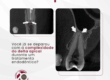

Quando um dente sofre um trauma, a vitalidade pulpar pode ser comprometida, mas nem sempre o teste de sensibilidade fornece uma resposta definitiva. Neste caso, o paciente apresentava um teste inconclusivo. Por isso, temos a tomografia como aliada em casos pós-trauma.

A tomografia computadorizada de feixe cônico (CBCT) revelou um conduto radicular calcificado, mas sem lesão periapical associada. Essa informação tornou-se determinante para a conduta clínica: não havia, naquele momento, indícios de necrose, e o caso encaminhou-se para acompanhamento tomográfico.

Por que a tomografia foi essencial nesse cenário?

✔ Confirmou a integridade dos tecidos periapicais, permitindo uma conduta mais conservadora.

✔ Estabeleceu um parâmetro para comparações futuras, auxiliando na decisão sobre necessidade ou não de intervenção.

A tomografia fornece dados objetivos para um diagnóstico mais seguro e uma abordagem baseada em evidências.